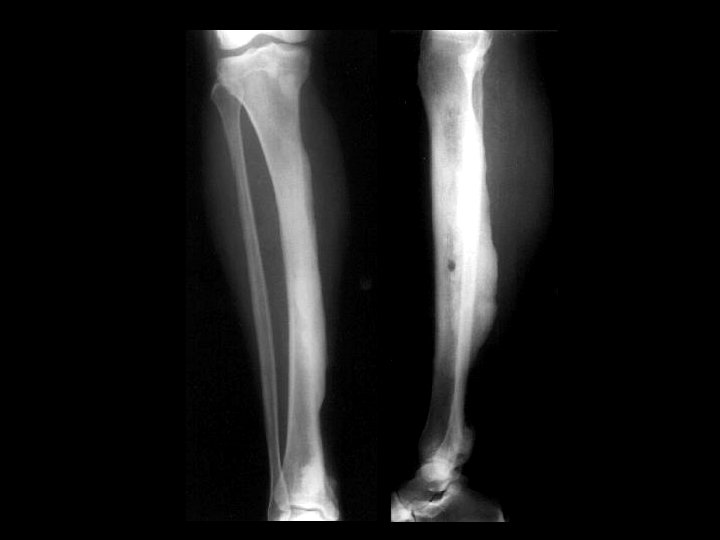

Aneurysmal bone cyst • Findings: – Lucent end of bone lesion in the proximal tibia – Slightly expansile, mild periosteal reaction – Fluid-fluid level on MRI • ddx: – Giant cell tumor – Unicameral bone cyst – Fibrous dysplasia – Chondroblastoma (rare)